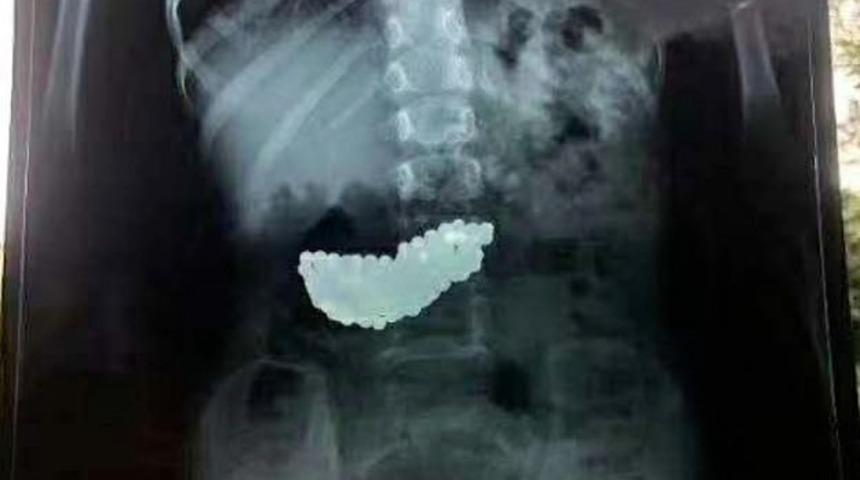

Mıknatıslı olan bilyeler çocuğun midesinde biraraya gelerek büyük bir kitle haline geldi. Bilyeler doğal yollardan çıkmayınca küçük kız 2 ay bu kitleyle yaşadı. Doktorlar rontgenle tespit ettikleri kitleyi ameliyatla çıkardı.